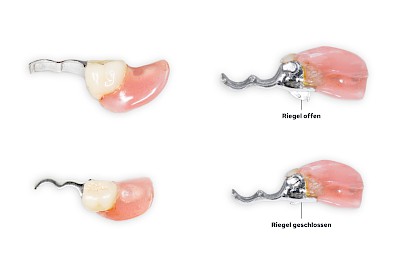

Manchmal sind Zahnprothesen auch über komplizierte Verankerungselemente (Riegel) mit den Restzähnen verbunden. Zudem werden nicht selten die verschiedenen Verbindungselemente kombiniert. Teilprothesen sind sehr vielfältig und zum Teil technisch sehr aufwendig gefertigt. Deshalb ist auch die Handhabung (Einsetzen, Herausnehmen, Reinigen) nicht immer einfach und selbsterklärend. Wenn immer möglich, sollte der betroffene Mensch selbst seine Prothesen entnehmen und einsetzen – meist haben diese jahrelange Übung und kennen die "Tricks"

Beispiele mit Riegelelementen bzw. Monoreduktoren 48 Bilder

Abzugshilfen

Das Herausnehmen von Zahnprothesen ist mitunter schwierig. Grundsätzlich können leichte Rüttelbewegungen das Herausnehmen erleichtern. Die Prothese sollten immer gut – am besten auf beiden Seiten gleichzeitig – mit Daumen und Zeigefinger gehalten werden, damit die Prothese nicht unbeabsichtigt aus den Fingern nach hinten in den Rachen fällt. Bei Klammerprothesen sollte direkt an den Klammern von unten angesetzt und gleichzeitig von oben gegengehalten werden. Bei Riegelprothesen müssen zunächst die Riegel (in der Regel gibt es zwei Riegel – einen auf der linken und einen auf der rechten Seite) geöffnet werden. Wenn sich die Prothese festhakt, ist es am besten, die Prothese einfach wieder zurückzudrücken und erneut einen Versuch zu starten.

Manchmal werden an den Prothesen auch spezielle Abzugshilfen eingearbeitet. Kompressen als Hilfsmittel können geeignet sein und schließlich gibt es auch im Handel sogenannte Prothesenabzieher.

Klemmt eine Prothese oder bestehen Unsicherheiten beim Herausnehmen, sollte ein Zahnarzt gerufen werden.